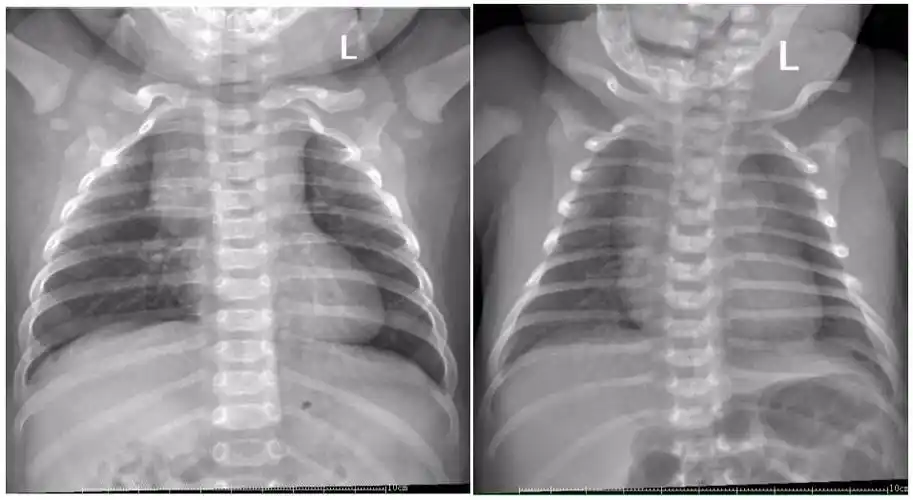

这几组患儿胸片是肺炎还是正常影像规培医师懵了